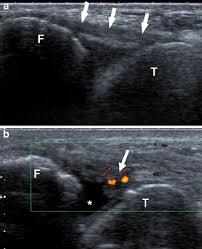

전거비인대는 "발목 바깥 복숭아뼈와 발목뼈 사이를 잇는 얇은 띠"로, 초음파에선 선명한 섬유줄처럼 보입니다.

파열 시엔 "연속성이 끊기고 두꺼워지거나 검게 벌어진 공간"이 보입니다.

회복되면 "끊김이 줄고 섬유가 다시 이어지며 부종이 감소"합니다.

3. 회복되면 초음파에서는 어떻게 보이는가

회복 과정에서 초음파는 다음과 같이 변합니다.

A. 부종(검은 부분)이 감소해 인대 주변이 정돈됨

B. 흐릿했던 인대 섬유가 조금 더 균일한 밝기를 띠게 됨

C. 끊겼던 섬유가 완전히 원래처럼 보이진 않지만,

연속성 있는 밝은 띠 형태로 복원됩니다.

D. 장기적으로는 약간 두꺼워진 조직(흉터화)처럼 보일 수 있음

인대는 파열 후 처음 모습으로 “완전 동일하게” 돌아가지는 않지만, 기능적으로 충분히 회복되는 경우가 대부분입니다.